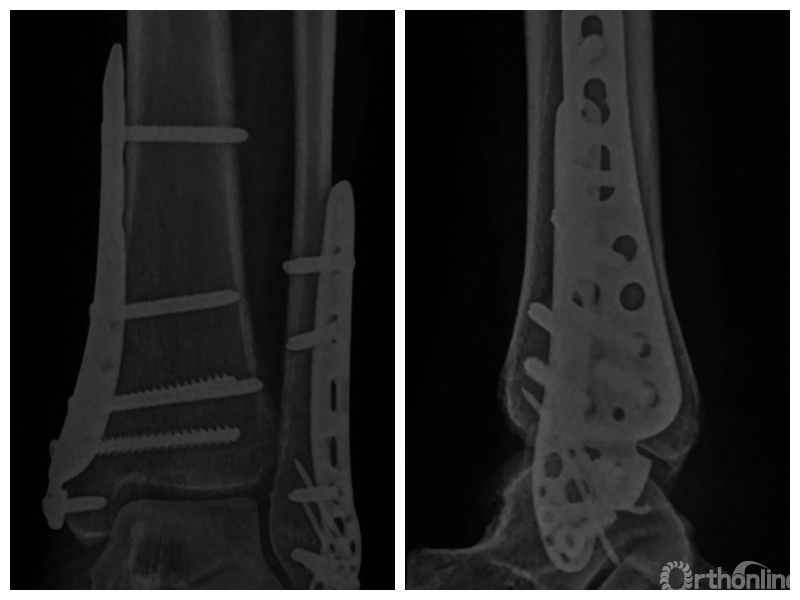

两组患者均获随访,支撑钢板固定组随访时间46~91,平均64.5个月;螺钉固定组随访时间44~86,平均59.5个月。支撑钢板固定组患者术后完全负重时间为(11.5±1.6)周,较螺钉固定组的(12.6±2.3)周显著缩短,比较差异有统计学意义(t=2.05,P=0.04)。X线片复查示,支撑钢板组均获解剖复位,均达愈合;螺钉固定组有20例获解剖复位,2例畸形愈合,1例不愈合,支撑钢板组骨折愈合时间为(11.5±1.6)周,螺钉固定组为(12.0±1.7)周,比较差异无统计学意义(t=1.06,P=0.30)。见图1、2。支撑钢板固定组3例(10%)、螺钉固定组4例(17.4%)发生创伤性关节炎,均采取保守治疗;两组比较差异无统计学意义(P=0.45)。

图1 支撑钢板固定组患者,女,63岁,右侧旋后-内收型II度踝关节骨折 a. 术前正侧位X线片;b. 术前CT;c. 术后2周正侧位X线片;d. 术后2年正侧位X线片

图1c 术后2周正侧位X线片

图1d 术后2年正侧位X线片

图2 螺钉固定组患者,女,37岁,左侧旋后-内收型II度踝关节骨折 a. 术前正侧位X线片;b. 术前CT;c. 术后2周正侧位X线片;d. 术后1年正侧位X线片

图2c 术后2周正侧位X线片

图2d 术后1年正侧位X线片